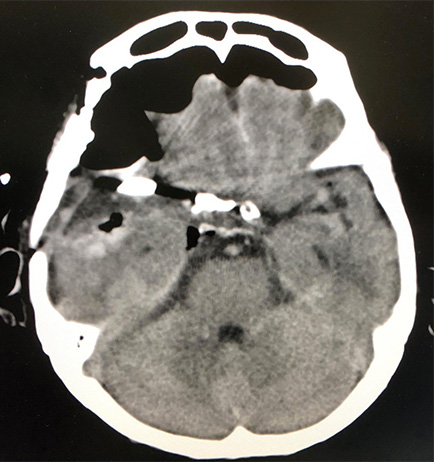

術前CT

術後二日目CT

大型の破裂動脈瘤に対し開頭クリッピング術を施行。脳梗塞等合併症が起こる事なく退院されています。術前CTで認められるくも膜下出血は術後に反対側や、後頭蓋窩まできれいに洗浄除去されています。